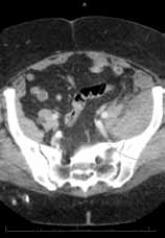

ArticleCase Report: Spontaneous Retroperitoneal Bleeding Masking as Left Lower Quadrant Abdominal PainAuthor:Edwin Lui, DOPublish date: April 1, 2015 A rare but serious condition, spontaneous retroperitoneal bleeding often presents with a variety of nonspecific symptoms, which in the absence of ...Read More